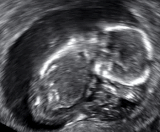

A 13-week fetus without cardiac activity located in the uterus (delayed or missed miscarriage)

A missed miscarriage is when the embryo or fetus has died, but a miscarriage has not yet occurred. It is also referred to as delayed miscarriage, silent miscarriage, or missed abortion.[98][99]